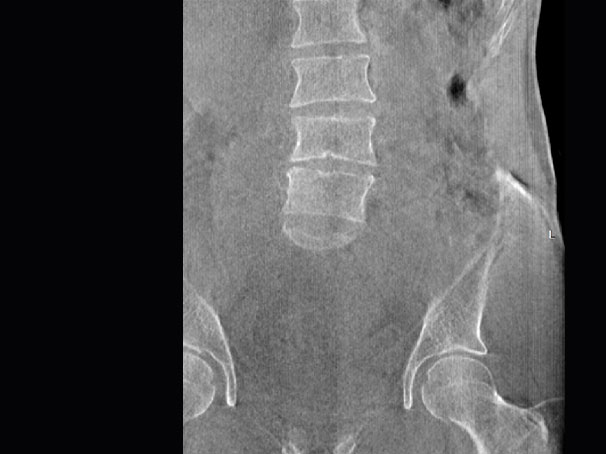

髋关节

腰椎